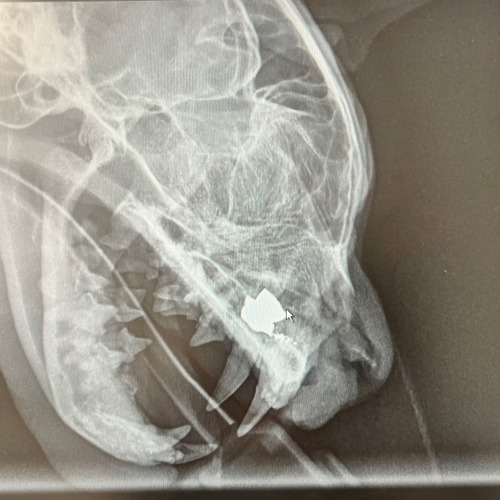

Leo's x-ray showing the air gun pellet

There was shock all round when the root of the problem was revealed to be an air gun pellet. With no visible entry wound, it was determined poor Leo must have been shot some time ago.